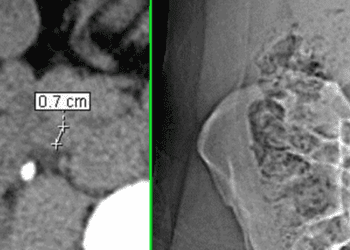

Your doctor will check your urine for red blood cells. He or she may order a computed tomography (CT) scan or ultrasound. The CT scan can show an actual stone. The ultrasound usually cannot detect the actual stone. But an ultrasound can show swelling of the kidney and/or ureter which indicates that the stone is obstructing urine flow.

Contrast-enhanced computed tomography associated with high sensitivity to renal stone detection

Non-contrast CT sensitive and specific for kidney stones [Classics Series]